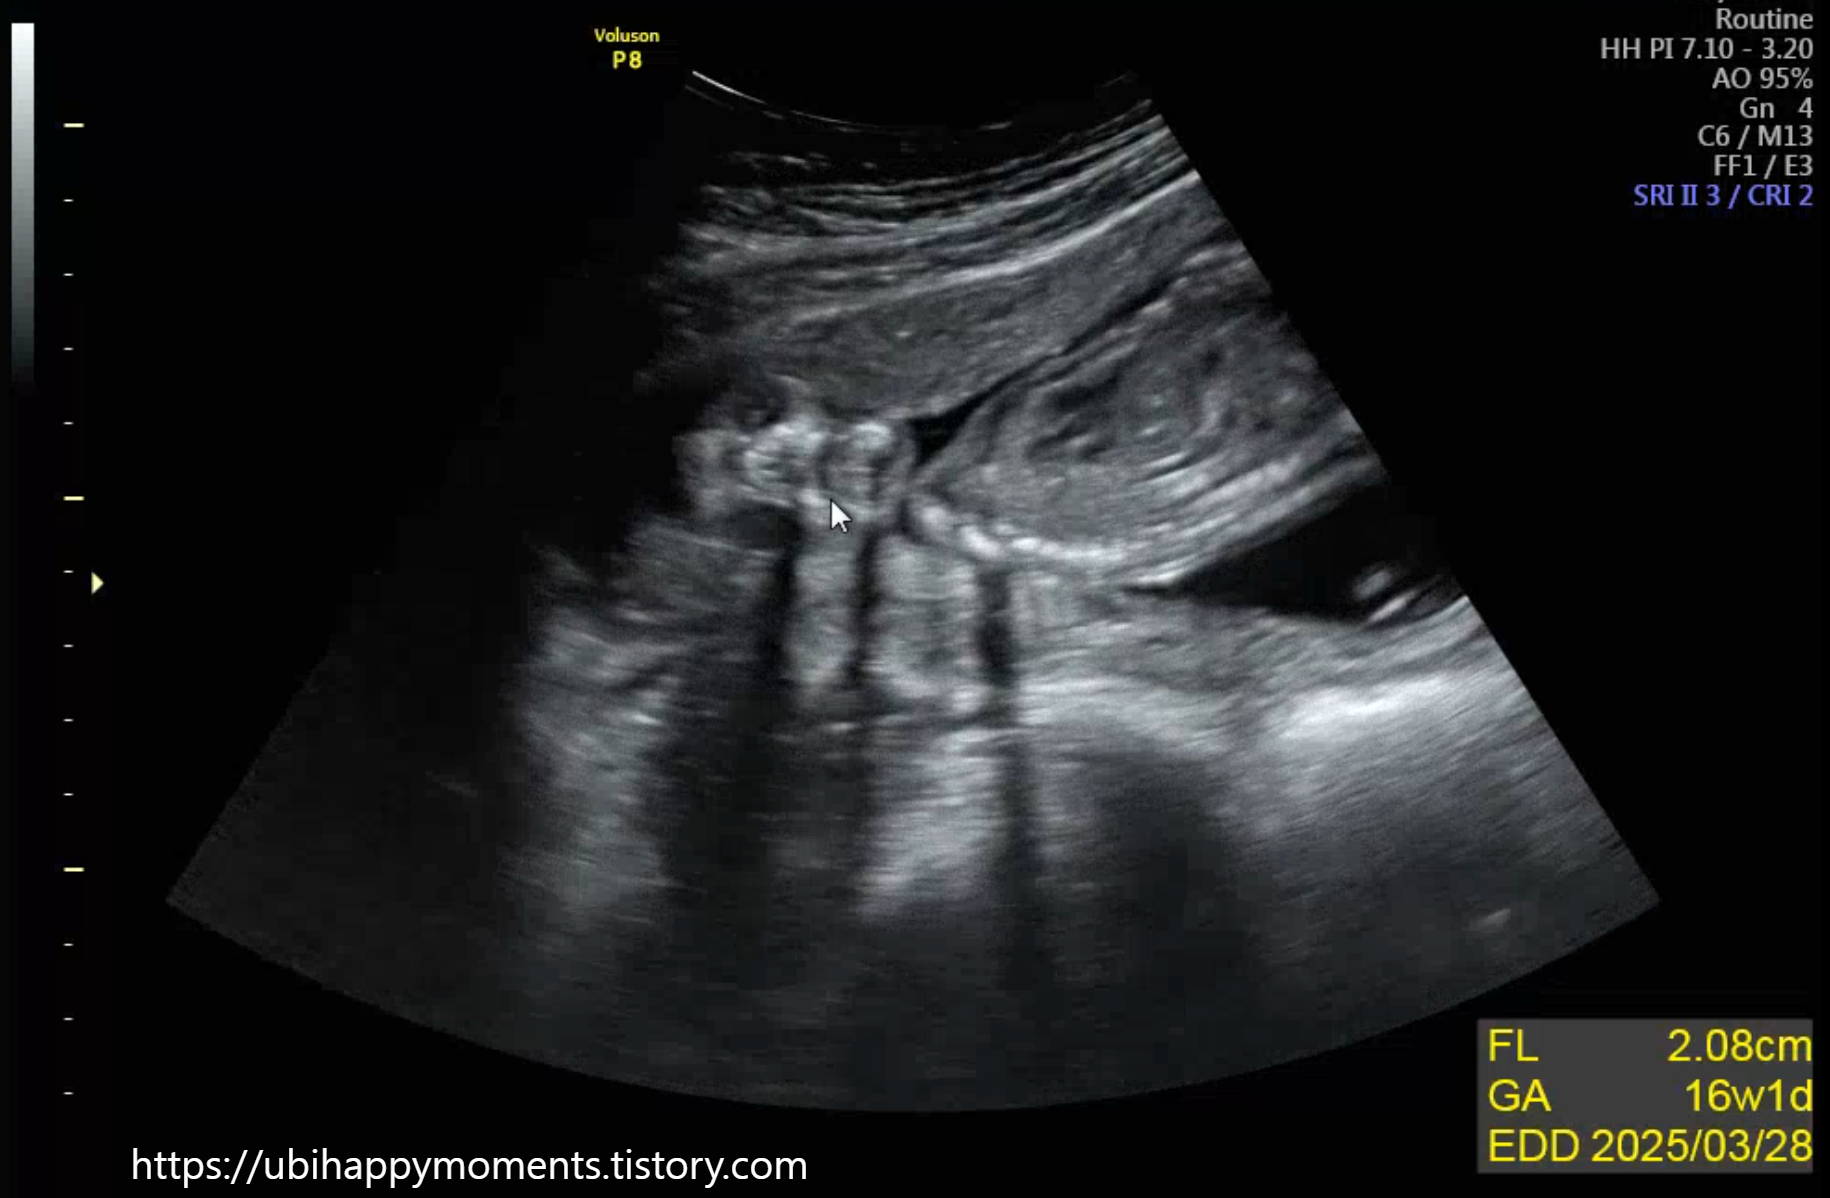

16주 차에 2차 기형아 검사를 받았습니다!

'초음파 검사'를 통해

태아의 신체적인 기형이 있는지 없는지 확인합니다.

2차는 일반 초음파로 확인하더라고요!

그 밖에도 손가락, 발가락 개수 확인, 태반의 위치, 양수량, 등

정밀 초음파 못지않게 상세히 다 봐주십니다!

16주 차쯤 되면

딸은 생식기가 점점 몸속으로 들어가고,

아들이면 밖에서 형성이 된다고 합니다.